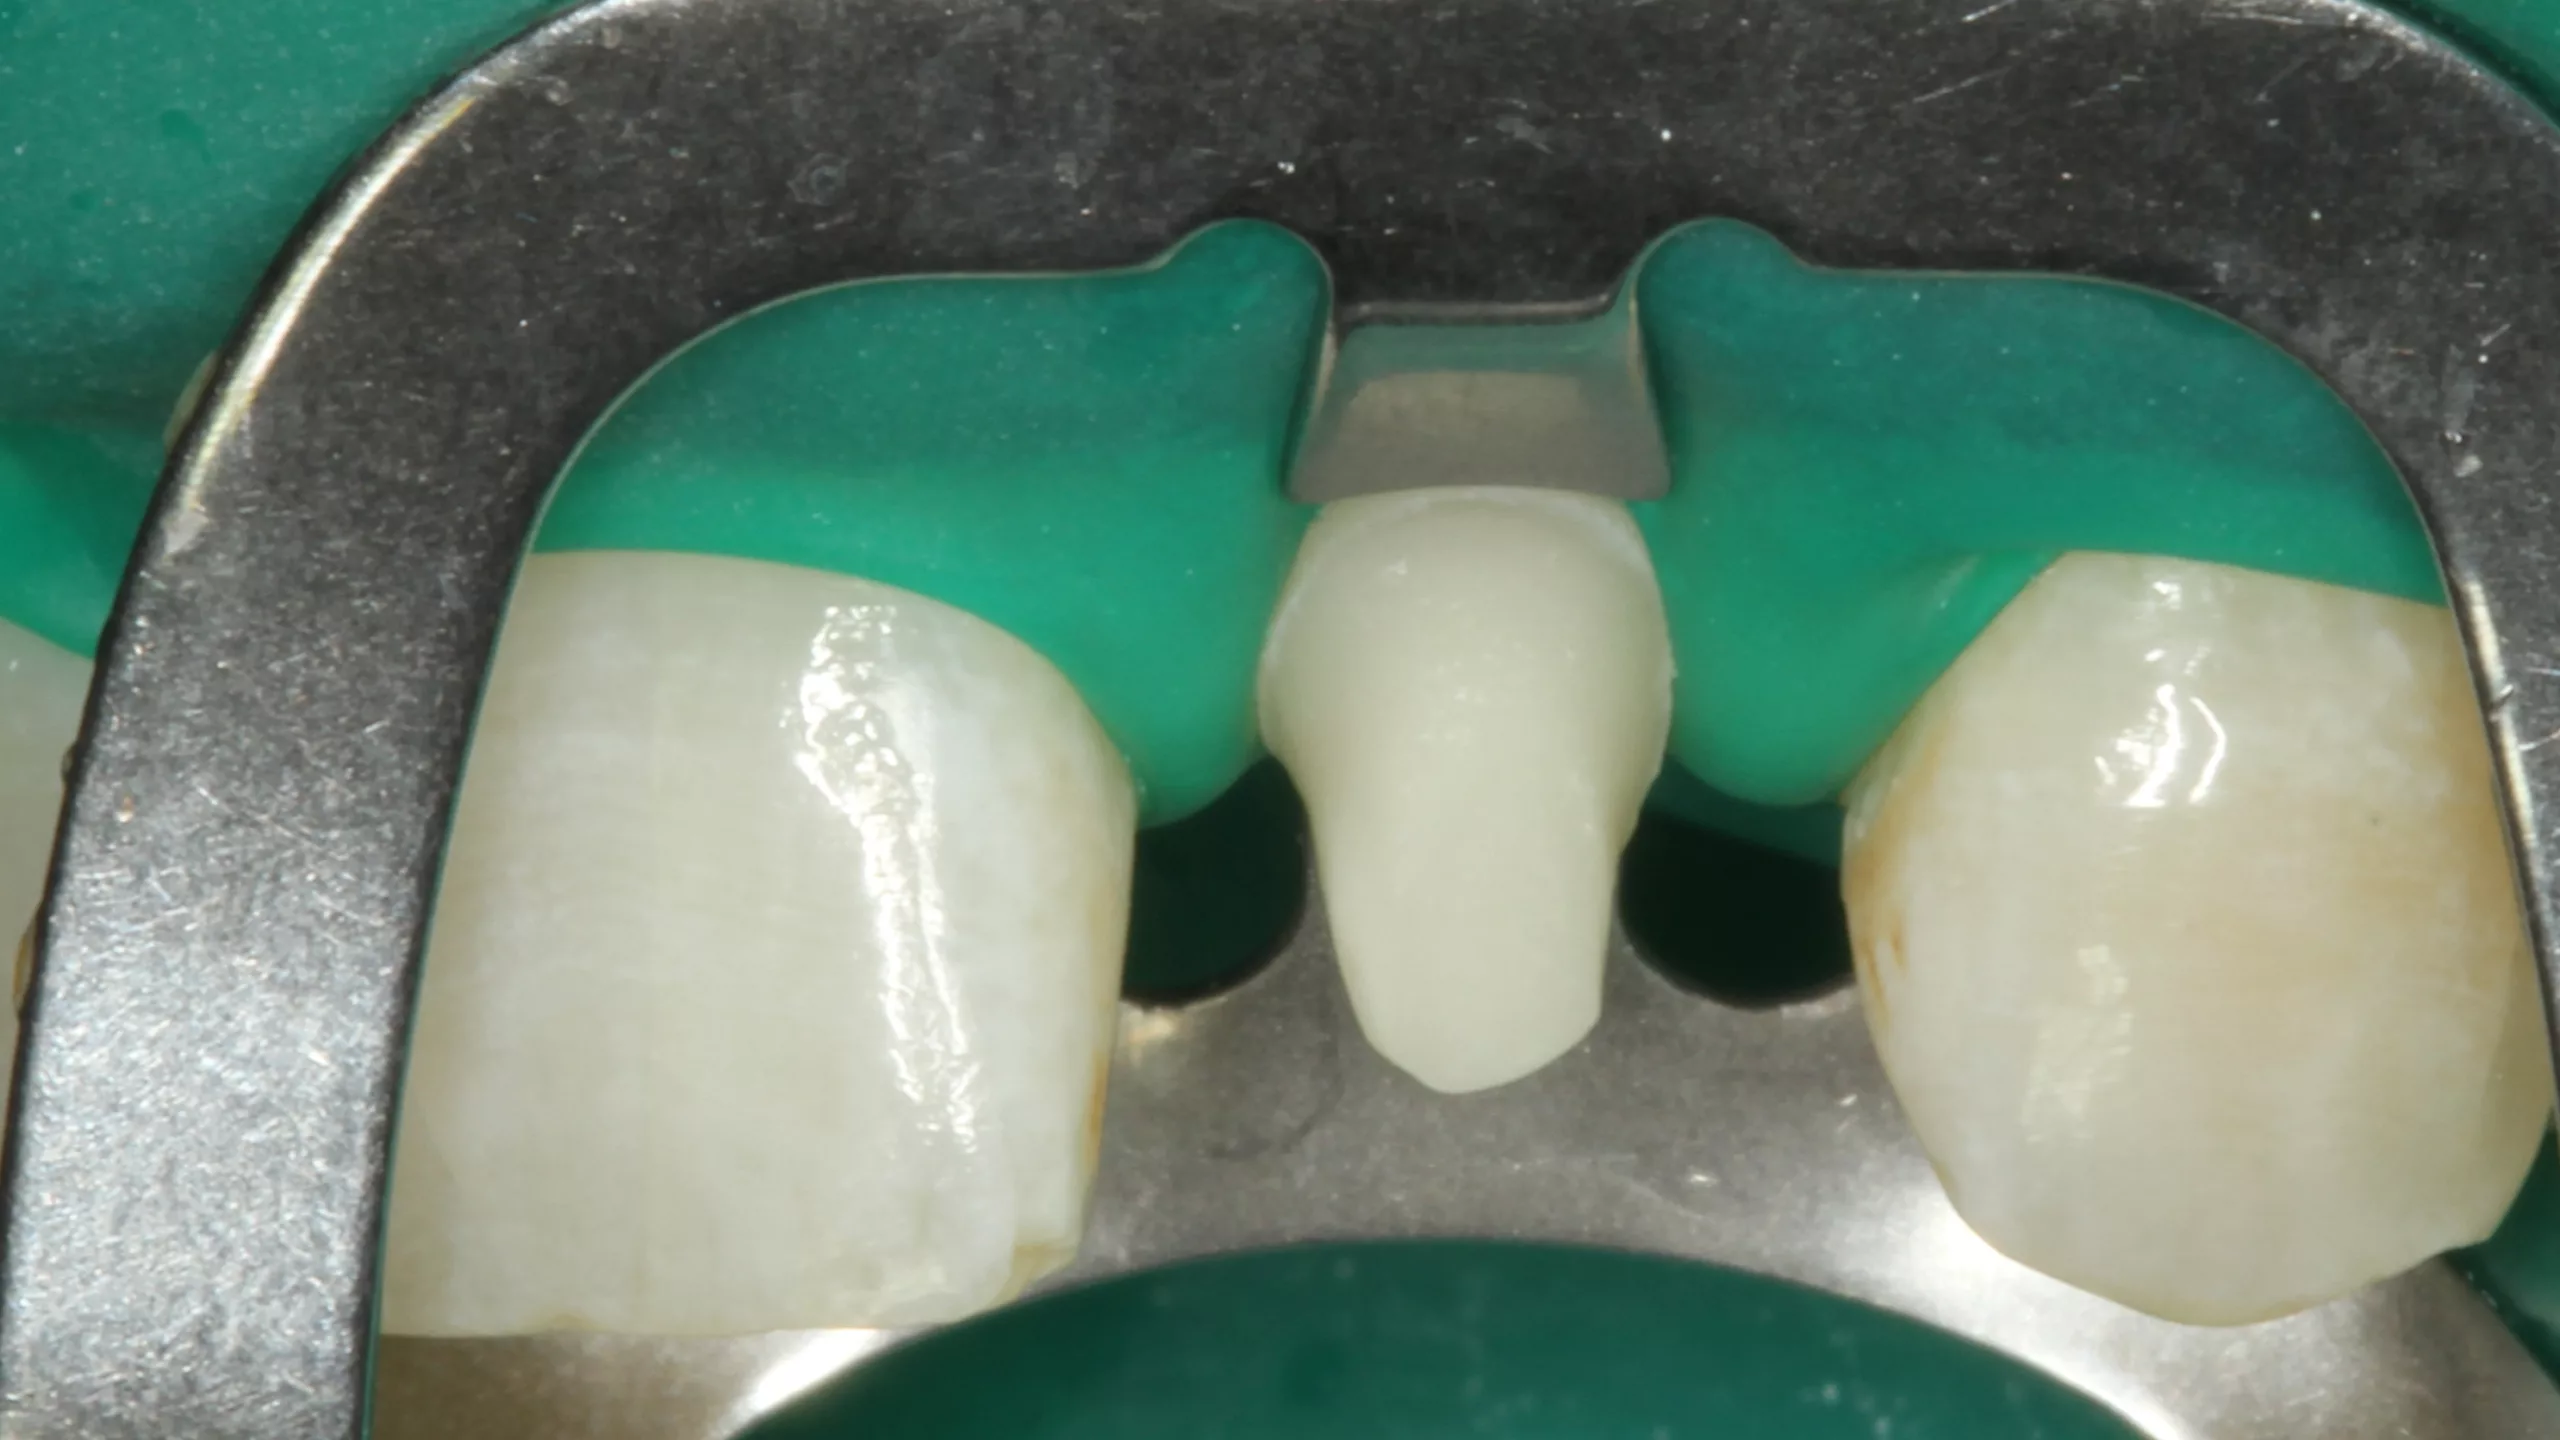

Die Abbildung 19 zeigt den bereits mit Kofferdam isolierten Zahn 22 nach der Reinigung der Oberfläche, die Abbildung 20 die Phosphorsäurekonditionierung der gesamten Klebefläche (Schmelz- und Dentinareale ließen sich nur schwer voneinander optisch differenzieren). Da der Visalys Tooth Primer auf mit phosphorsäuregeätztem Dentin genauso effizient funktioniert wie in seiner originären, selbstkonditionierenden Primerfunktion, sollte im Zweifelsfall besser großräumiger mit dem Phosphorsäuregel geätzt werden. Die Abbildung 21 zeigt den konditionierten Zahnstumpf aus inzisaler Sicht, die Abbildung 22 von labial. Wie in allen vorangegangenen Fällen erfolgte im nächsten Schritt die Applikation des Visalys Tooth Primers, dessen Einwirken für 20 Sek. (Abb. 23 und 24) und das Verblasen der Überstände bzw. die sorgfältige Evaporation des Lösungsmittels mit dem Luftbläser. Mit diesem Schritt war die Vorbehandlung des Zahnes abgeschlossen. Auch diese Krone wurde mit Visalys CemCore in der Farbe Universal (A2/A3) adhäsiv befestigt. Die vollständige Überschussentfernung erfolgte erneut mit einem sauberen Bondingpinsel (kein Microbrush) noch vor der Polymerisation (Abb. 25). Die Abbildung 26 zeigt die versäuberte, eingeklebte verblendete Vollzirkonkrone noch unter Kofferdam, die Abbildungen 27 und 28 das finale klinische Gesamtergebnis der sehr zufriedenen Patientin.